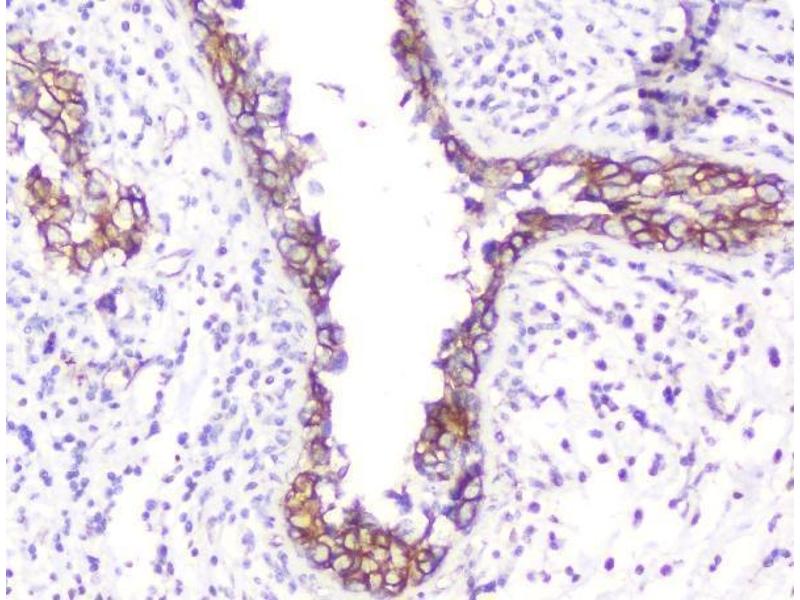

Choisissez l’un des 247 anticorps CTNNB1 de notre liste de produits basés sur 68 publications et 314 images de validation.

Découvrez des anticorps CTNNB1 fiables issus d’une large sélection de fabricants renommés. Notre portefeuille permet une détection précise de CTNNB1 dans plusieurs espèces, y compris Human, Mouse, Rat, Dog, Monkey, Chicken, Cow, Zebrafish (Danio rerio), Pig, Horse, Rabbit, Xenopus laevis, Hamster, Bat, Guinea Pig, Sheep, Opossum, et prend en charge diverses applications de recherche telles que WB, IHC, ELISA, IF, FACS.